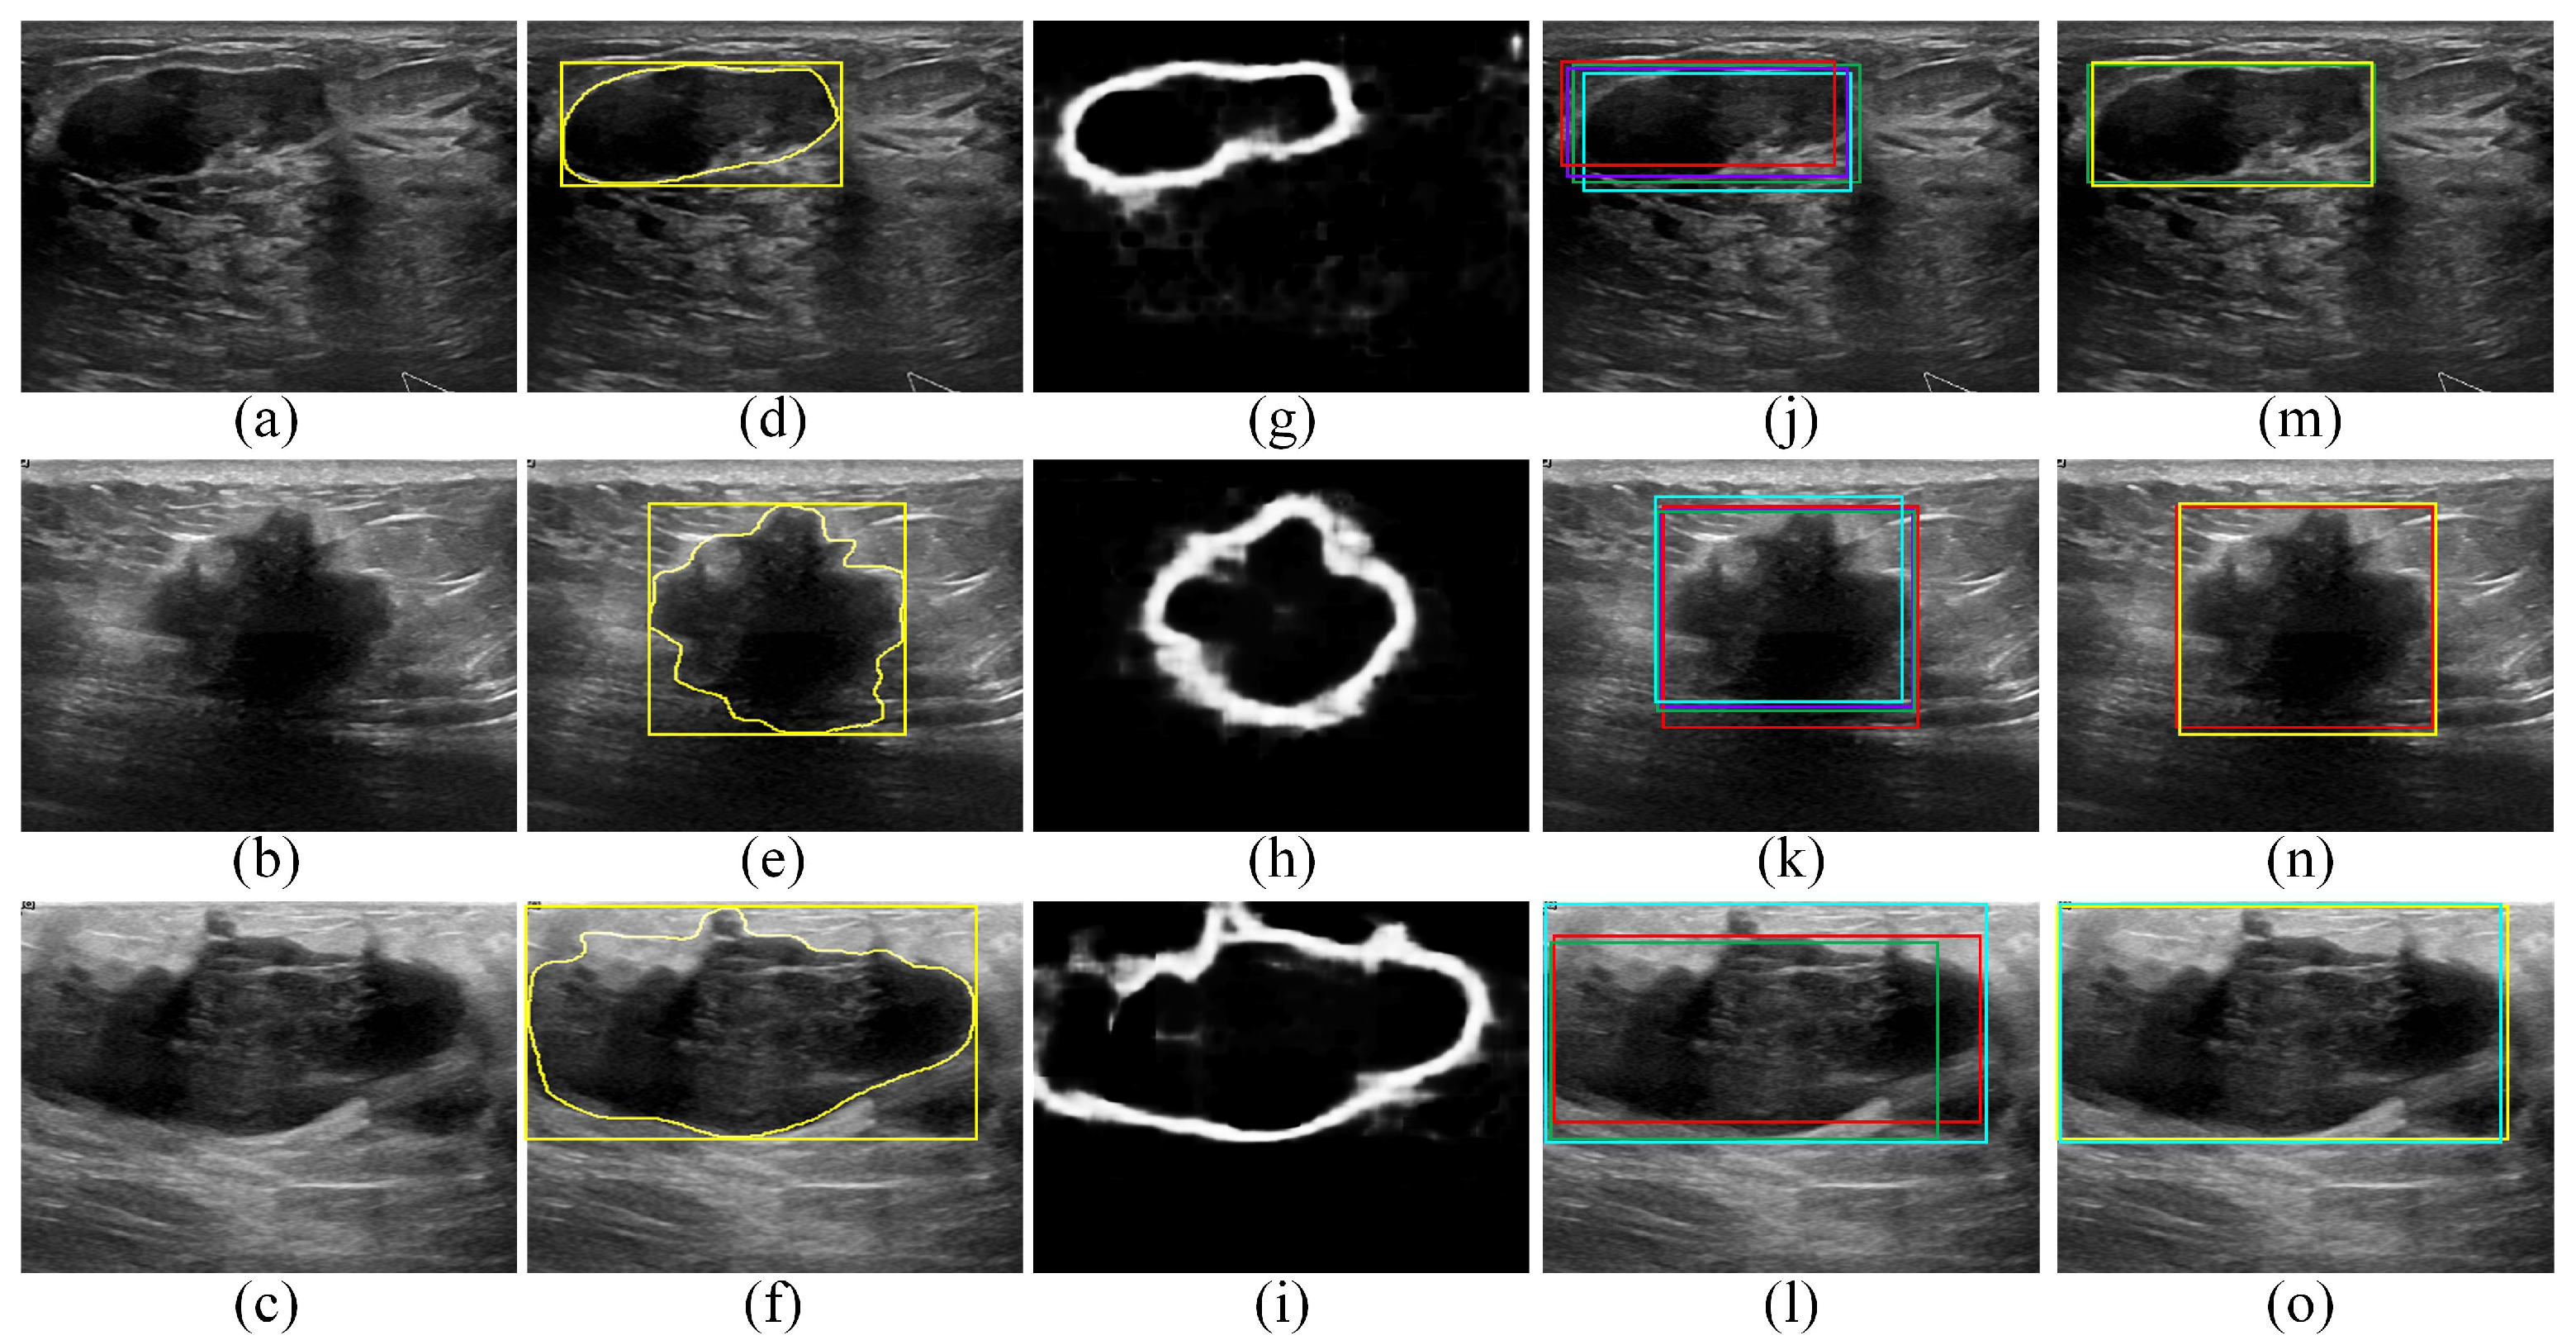

2.2.1. Transforming the BUS Images into Artificial RGB Images

2.2.2. Employing the Faster R-CNN Model to Localize ROIs That Contain the Tumors

2.2.3. Employing the SSD Model to Localize the ROIs That Contain the Tumors

2.2.4. Employing the EfficientDet-D0 Model to Localize ROIs That Contain Tumors

2.2.5. Employing the CenterNet Model to Localize ROIs That Contain Tumors

2.2.6. Employing the Proposed Edge-Based Selection Method to Select ROIs That Enable the Effective Detection of Regions That Contain Tumors